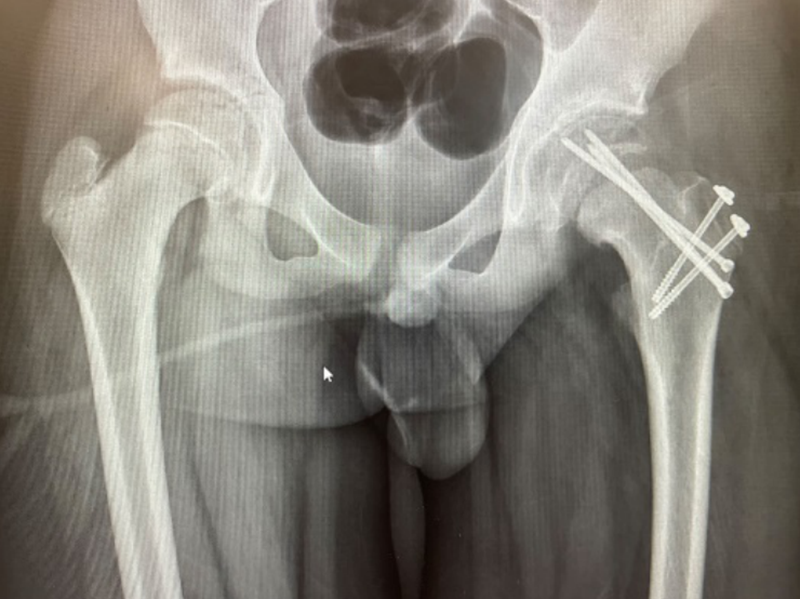

住院期間,醫(yī)生團隊早晚查房,密切觀察病情變化;護理團隊認真負責,悉心呵護。全科醫(yī)護人員以和藹可親、熱情周到的服務(wù),不辭辛勞、不怕麻煩的精神,贏得了患者及其家屬的贊譽。看著患者術(shù)后的X片,患者家屬激動地說:“感謝柳人醫(yī)創(chuàng)傷骨科團隊,你們的技術(shù)一流,醫(yī)德醫(yī)風也很好,把我們這么難治的病都治好了。”

術(shù)后X片影像

此次進行的改良Dunn手術(shù)技術(shù)難度大,操作時間長,是個精細手術(shù)。手術(shù)過程中需要保護供應(yīng)股骨頭的主要血管,避免出現(xiàn)股骨頭壞死,因此手術(shù)需要很精細的操作,這是手術(shù)的一大難點,但是手術(shù)成功后,就能良好恢復(fù)關(guān)節(jié)的功能。術(shù)后經(jīng)過專業(yè)的康復(fù)指導(dǎo)后,孩子的走路姿勢就基本和正常人一樣了。